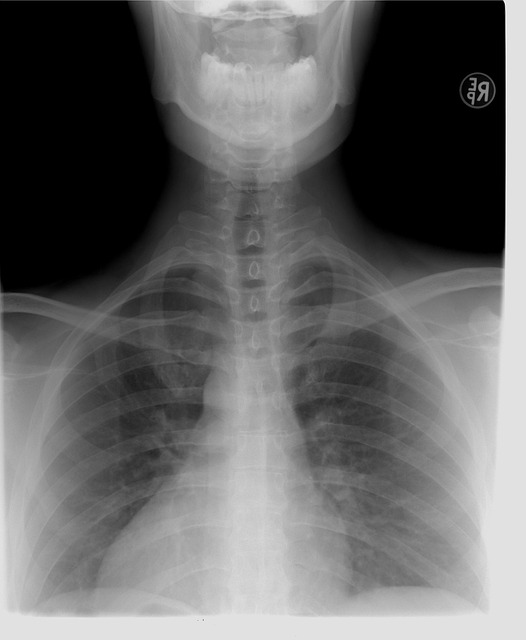

Skolióza páteře